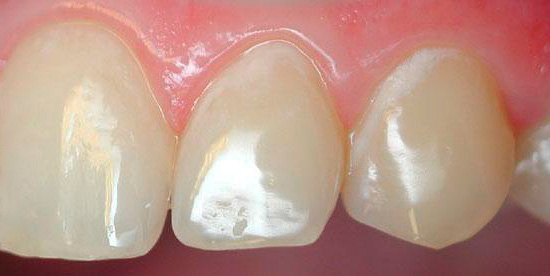

L'ispezione visiva dei denti è il modo principale per identificare una situazione cariogena nella cavità orale. La carie è caratterizzata dal fatto che in quasi tutte le fasi del suo corso, cambia il colore dello smalto dei denti. Anche nella fase spot, quando la dentina non è ancora interessata, lo smalto cessa di essere liscio e lucido e il dentista attento nota facilmente un tale cambiamento.

In fasi successive, determinare la carie con un semplice esame è ancora più semplice: porta alla comparsa di punti neri e marrone scuro sui denti o quando la dentina è danneggiata, sotto lo smalto sono visibili cavità scure.

È la diagnosi visiva più disponibile a casa e ti consente di riconoscere tu stesso la patologia dei denti. Basta solo esaminare attentamente i denti allo specchio. Vale la pena non solo cercare aree francamente nere, ma anche prestare attenzione a tutti i luoghi che si stagliano sullo sfondo di denti bianchi puri. Ricorda: le aree nere e marroni indicano un danno sufficientemente profondo al dente (nel migliore dei casi, solo lo smalto sarà pigmentato). Un tale dente dovrà probabilmente essere forato, forse anche un nervo verrà rimosso da esso. Pertanto, il dentista dovrebbe essere consultato anche prima della comparsa di un danno visibile significativo.